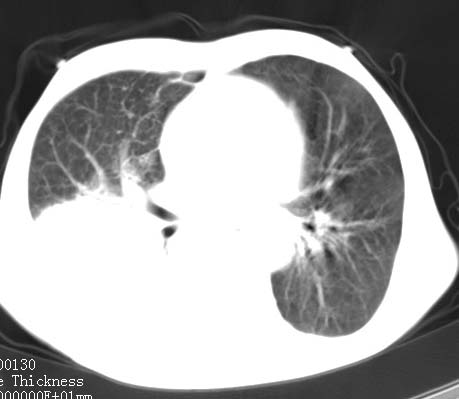

病人女 60岁 咳嗽 气促十余天,大叶性肺炎.

右肺上下叶均见 大片状密度增高影,边界清晰,其内可见支气管充气征,气管支气管通畅。纵膈略向右移位,其内无肿大淋巴结影。首先考虑炎性病变。不排除一些特异性的炎症。不知道发烧吗??wbc高吗??建议治疗后复查!!